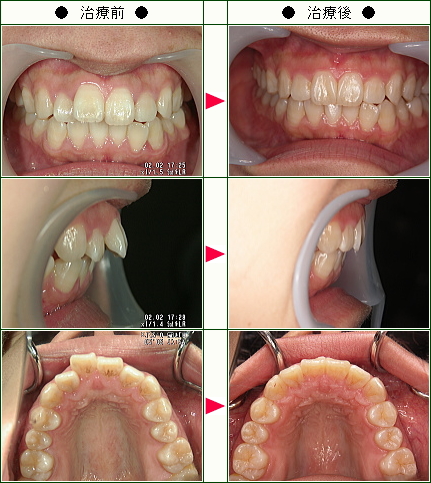

☆歯のデコボコ矯正症例(N.I様 35歳 女性)

ワイヤーを付けていた期間は3カ月で、あっという間にずっと気になっていた歯並びが綺麗になり感動しました。

痛みなど、少し辛かったこともありましたがすぐに慣れました。

担当の方が親切、丁寧で、とても感じが良いので安心して通うことができました。

もっと早くやっておけばよかったと後悔している程です。